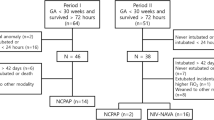

We evaluated 70 infants born at < 30 weeks’ gestation in a primary screen, of whom 46 cases met eligibility and consented to participate. Out of the 46 consented patients, 40 infants completed the study protocol (20 infants in each group). Six infants (4 cases in the NIPPV group and 2 infants from NIV-NAVA group) were not scanned due to timing issues and were excluded (Fig. 2). Baseline characteristics and respiratory status prior to the LU scanning of the two groups were summarized in Tables 1 and 2. There was no significant difference between the NIV-NAVA group compared to the NIPPV group regarding birth gestation (GA) or postmenstrual age (PMA) at the time of the scan. DE was significantly higher in NIV-NAVA [mean SD 4.7 (1.5)] versus [3.5 (0.9)] in NIPPV, p = 0.007 (Table 3). DTF was higher in NIV-NAVA compared to NIPPV group [mean (SD) 81.6 (30) vs 78.2 (27), p = 0.71). There was no significant difference regarding DTexp and DTins between groups. Both groups showed relatively high LUS but no significant difference [mean (SD) 12.8 (2.6) versus 12.6 (2.6) p = 0.8] (Fig. 3). Duration of IMV and incidence of BPD did not show significant difference between NIV-NAVA and NIPPV group [mean (SD) 5.35 (6.2) days versus 3.35 (4.4) days p = 0.24] and [80% versus 70% p = 0.85], respectively.